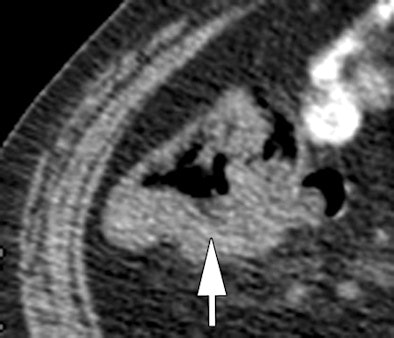

| Morphologic image (arrow, above) shows cecal cancer. Corresponding blood volume parametric maps show 40-mm2 ROI at tumor edge (below) and center (bottom). Images republished with permission of the Radiological Society of North America. Goh V, Halligan S, Gharpuray A, Wellsted D, Sundin J, Bartram CI. Quantitative assessment of colorectal cancer tumor vascular parameters by using perfusion CT: Influence of tumor region of interest. Radiology. 2008;247(3):726-732. |